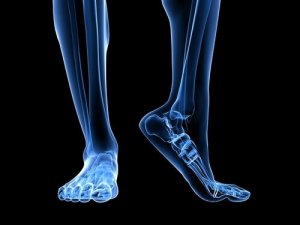

प्लांटर फेशियाइटिस पैर के तलवे में प्लांटर फेशिया की सूजन है। प्लांटर फेशिया एक लिगामेंट जो एड़ी की हड्डी को प्रॉक्सिमल फैलेंजेज से जोड़ती है और हर स्टेप के साथ रबर बैंड की तरह फैलती और सिकुड़ती है।

भारी प्रेशर और प्रतिरोध झेलने के कारण प्लांटर फेशिया (plantar fascia) एक बहुत व्यापक, मोटी टिशू है। इस लिगामेंट में सूजन होने से एड़ी में दर्द होता है। यह इस अंग में दर्द की सबसे अहम वजह है।

पैर की एनाटोमी

कई संरचनाएं हैं जो प्लांटर फेशिया को ओवरलोड करने में भूमिका निभाती हैं। अकिलीज़ टेंडन वह लिगामेंट है जो गैस्ट्रोनेमियस मसल्स यानी काफ और सोलियस मसल्स को एड़ी की हड्डी से जोड़ती है।

अकिलीज़ टेंडन के पीछे आने से एड़ी की हड्डी पर दबाव बढ़ जाता है, जिससे प्लांटर फेशियाइटिस पर भी दबाव बढ़ जाता है। इसका मतलब यह है कि आपके अकिलीज़ की स्ट्रेचिंग नहीं करने से फेशियाइटिस हो सकता है क्योंकि यह आपके पैर पर बहुत ज्यादा दबाव डालता है।

आपके शरीर की बनावट में ध्यान रखने वाली एक और बात फुट स्ट्राइक है। दूसरे शब्दों में इसका मतलब यह है की आपका पैर जमीन को कैसे छूता है। उदाहरण के लिए सपाट पैर वाले लोगों में प्लांटर फेशिया को ज्यादा खींचने का रुझान होता है। इससे इस टिशू पर ज्यादा दबाव पड़ने के कारण टूट-फूट का खतरा बढ़ जाता है।